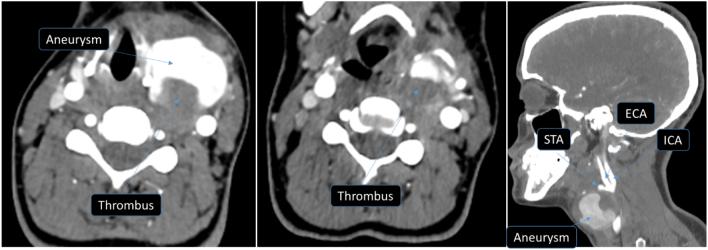

A 21-year-old female presented with anterior neck swelling of two years duration. Physical exam revealed a thyroid mass that measures 10 cm ∗ 8 cm. Neck US showed MNG (TIRADS 3) and FNAC suggested colloid goiter. Near Total Thyroidectomy was performed. On the 10th postoperative day, she noticed a painless, progressive left-sided neck swelling which is increasing in size with no active bleeding and no compressive symptoms. There is a 6x4cm tense pulsatile left-sided neck swelling adjacent to the thyroid cartilage and anterior to sternocleidomastoid muscle with a healed neck collar incision. CBC and coagulation profile were normal. Head and Neck CTA show aneurysmal dilatation of STA 3.8 cm × 3.2 cm with thrombosis of the posterior part of the lesion.

一名21岁女性,颈部前方肿胀已有两年。体格检查发现一个大小为10厘米×8厘米的甲状腺肿块。颈部超声显示为多结节性甲状腺肿(TIRADS 3类),细针穿刺活检提示为胶样甲状腺肿。遂行近全甲状腺切除术。术后第10天,她注意到左侧颈部出现无痛性、进行性肿胀,且肿胀面积不断增大,无活动性出血及压迫症状。在甲状腺软骨旁、胸锁乳突肌前方有一个6×4厘米大小、质地紧张、有搏动的左侧颈部肿胀,颈部领口切口已愈合。血常规和凝血指标正常。头颈部CT血管造影显示甲状腺上动脉动脉瘤样扩张,大小为3.8厘米×3.2厘米,病变后部有血栓形成。